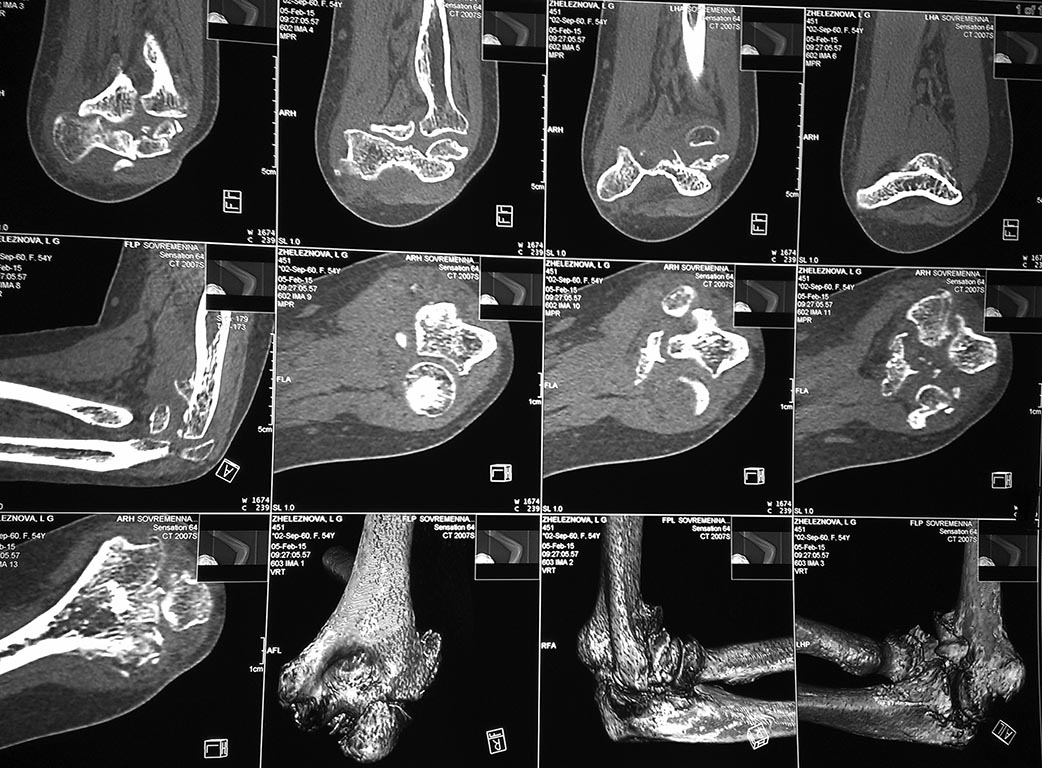

У женщины 54 лет имеются последствия закрытого вывиха костей предплечья...

Травма 08.11.14 г., окончательное вправление лишь 10.11.14 г., тогда же

появились признаки нейропатии локтевого нерва, они остаются до сих пор.

Движения в суставе качательные, практически анкилоз в положении 90 град.

Снимки КТ в приложении. Уважаемые травматологи-ортопеды! Что делать в

такой ситуации? Эндопротез? Релиз? Ничего?